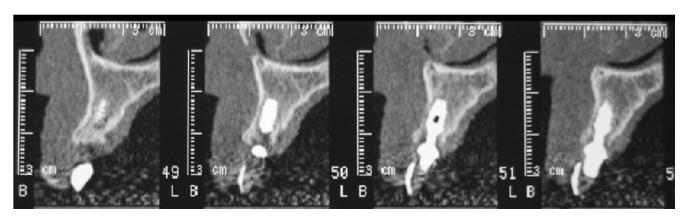

The functional and aesthetic restoration of teeth compromised due to aggressive periodontitis presents numerous challenges for the clinician. Horizontal bone loss and soft tissue destruction resulting from periodontitis can impede implant placement and the regeneration of an aesthetically pleasing gingival smile line, often requiring bone augmentation and mucogingival surgery, respectively. Conservative approaches to the treatment of aggressive periodontitis (i.e., treatments that use minimally invasive tools and techniques) have been purported to yield positive outcomes. Here, we report on the treatment and five-year follow-up of patient suffering from aggressive periodontitis using a minimally invasive surgical technique and implant system. By using the methods described herein, we were able to achieve the immediate aesthetic and functional restoration of the maxillary incisors in a case that would otherwise require bone augmentation and extensive mucogingival surgery. This technique represents a conservative and efficacious alternative to the aesthetic and functional replacement of teeth compromised due to aggressive periodontitis.

侵袭性牙周炎导致牙齿功能和美观受损,给临床医生带来诸多挑战。牙周炎引起的水平骨吸收和软组织破坏会妨碍种植体植入以及美观的牙龈微笑线的再生,通常分别需要进行骨增量和膜龈手术。据称,侵袭性牙周炎的保守治疗方法(即使用微创工具和技术的治疗方法)能产生积极效果。在此,我们报告了一名侵袭性牙周炎患者采用微创外科技术和种植系统的治疗及五年随访情况。通过使用本文所述方法,在原本需要骨增量和广泛膜龈手术的病例中,我们成功实现了上颌切牙的即刻美观和功能恢复。该技术是侵袭性牙周炎导致牙齿功能和美观受损时,一种保守且有效的替代治疗方法。